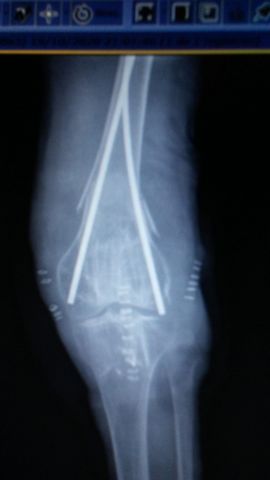

Tratamiento de fractura de radio con agujas.

|

Tratamiento con agujas de fractura de radio.